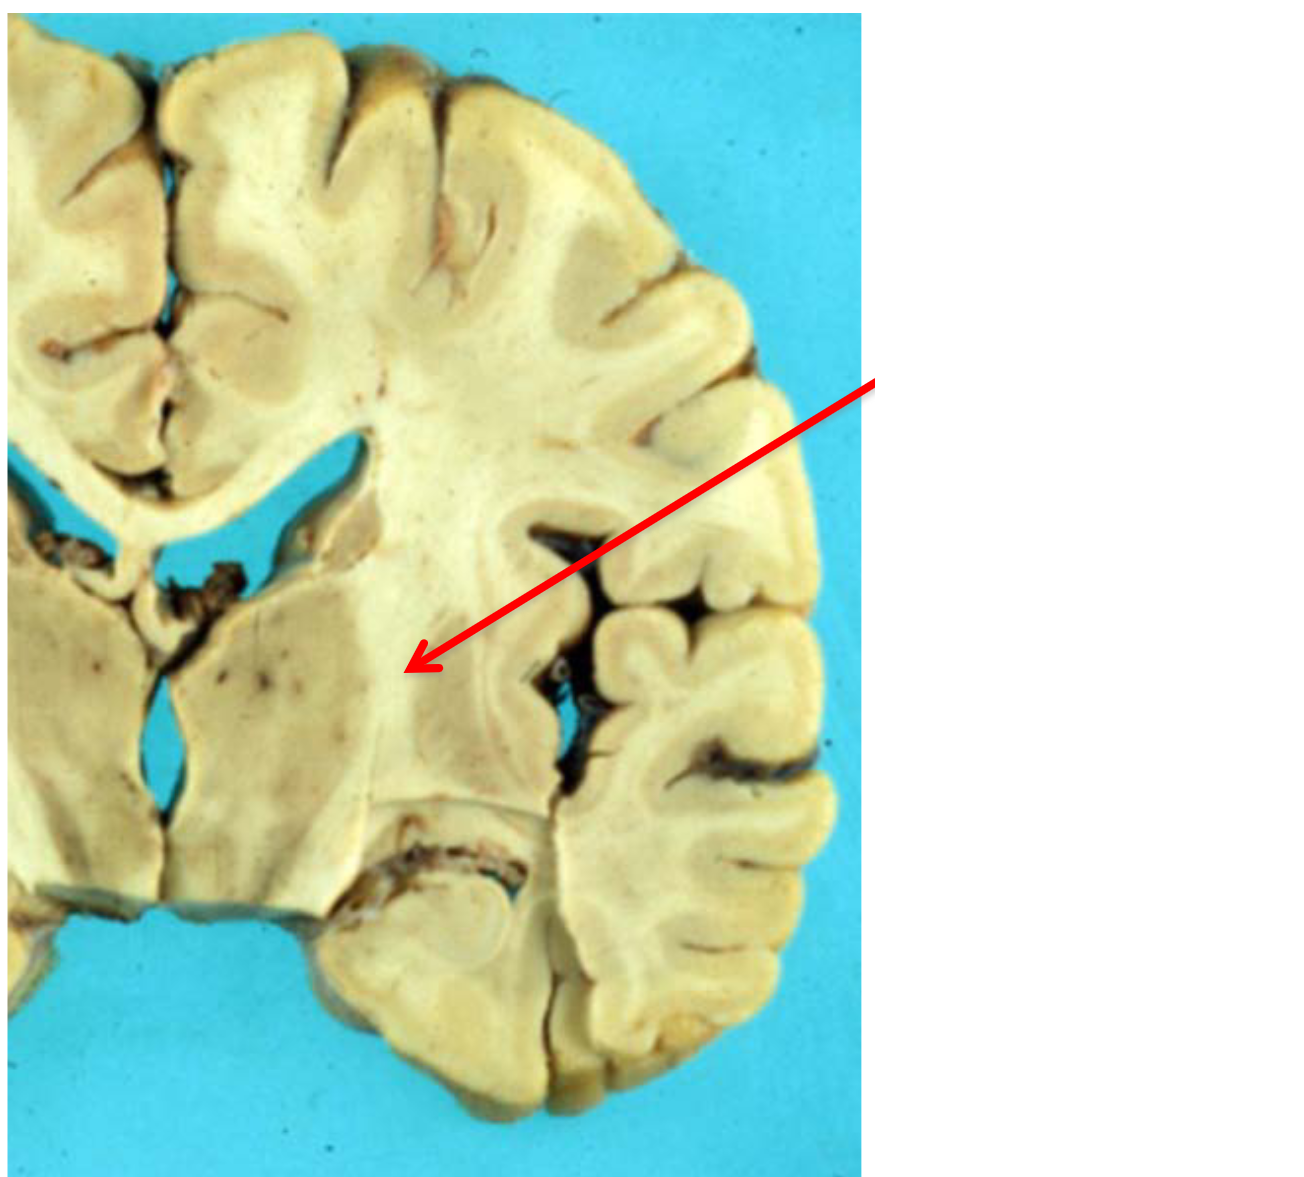

Q

internal capsule (coronal view)

A

How well did you know this?